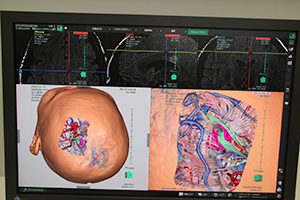

ITコーナーでは,3D画像解析システム「SYNAPSE VINCENT」の最新のバージョン4のソフトウエアを中心に展示した。泌尿器科領域での腎臓の腹腔鏡下手術シミュレーション,頭部の神経線維や血管などを表示した開頭手術シミュレーションなどのほか,モバイル端末への対応などをアピールした。そのほかSYNAPSEの新機能として,画像認識技術を使った骨ラベリング,肝臓がんに対応したSYNAPSE CaseMatchなどを紹介した。

SYNAPSE VINCENTの新しいソフトウエアを紹介。泌尿器科領域での腎臓の腹腔鏡下手術シミュレーション

神経線維や血管の情報を表示した脳腫瘍などの開頭手術の術前シミュレーション